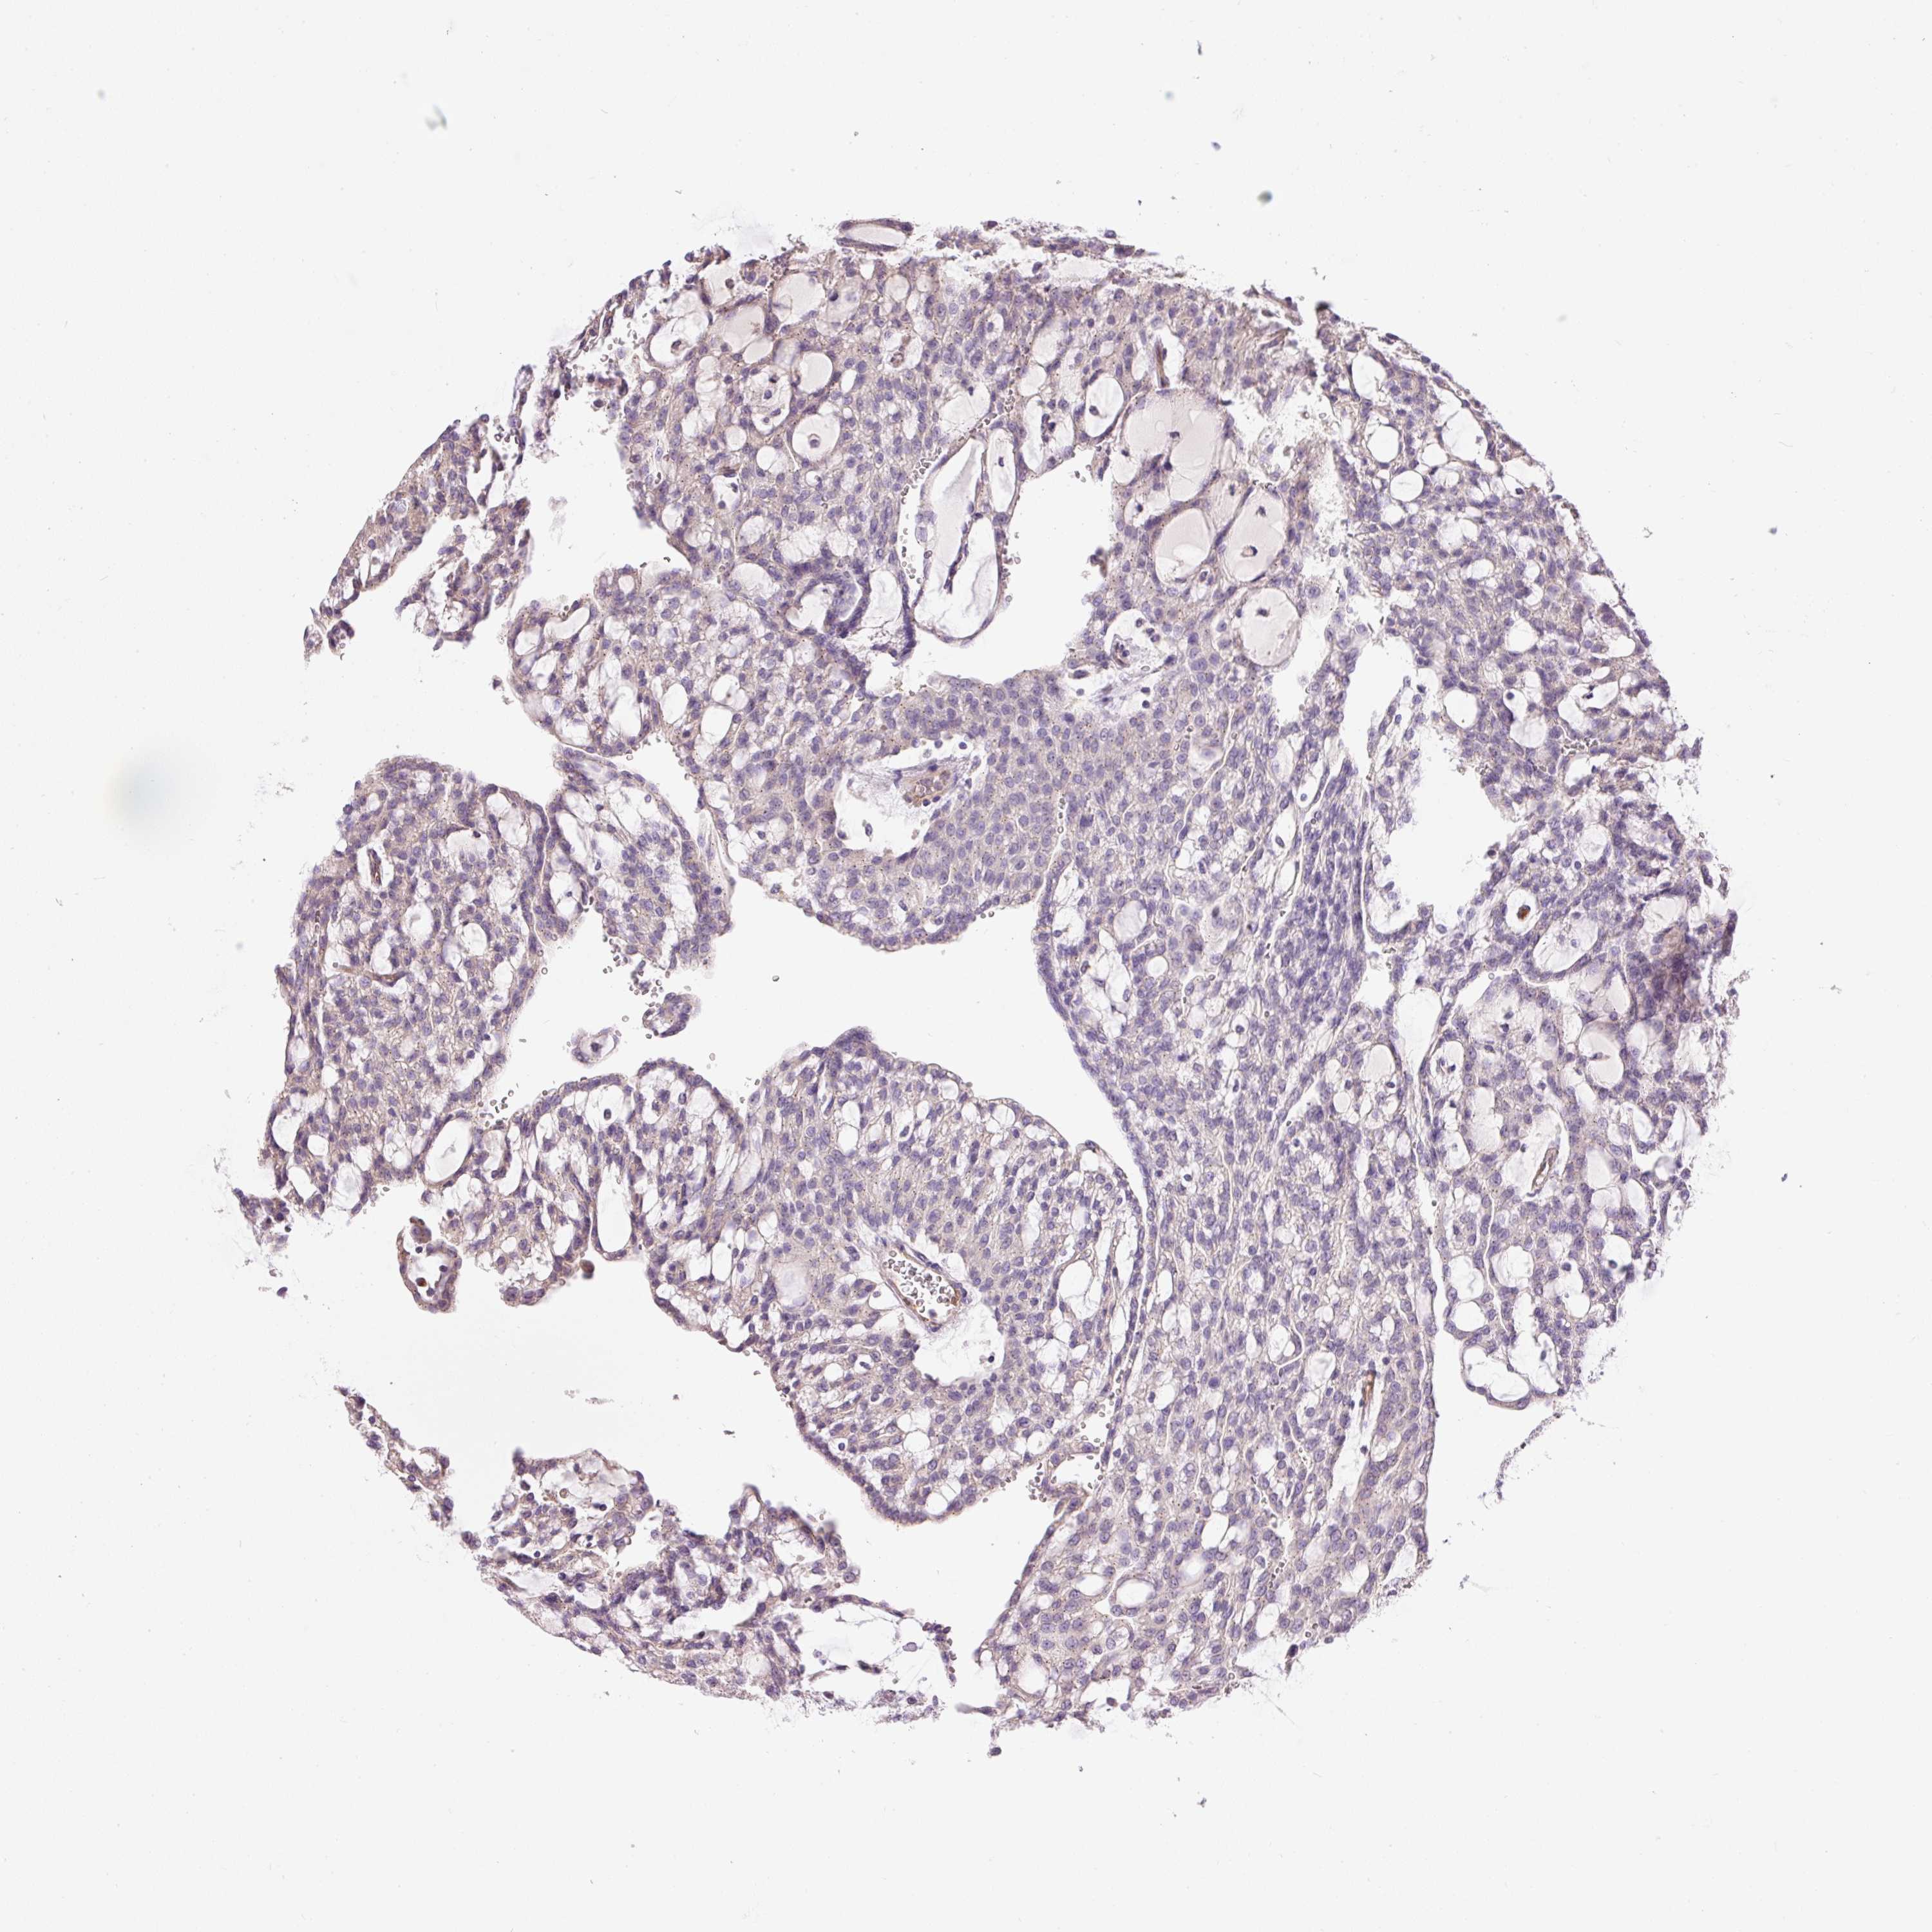

KIDNEY RENAL CLEAR CELL CARCINOMA (VALIDATION) - Interactive survival scatter ploti

The Survival Scatter plot shows the clinical status (i.e. dead or alive) for all individuals in the patient cohort, based on the same data that underlies the corresponding Kaplan-Meier plots. Patients that are alive at last time for follow-up are shown in blue and patients who have died during the study are shown in red.

The x-axis shows the expression levels (FPKM) of the investigated gene in the tumor tissue at the time of diagnosis. The y-axis shows the follow-up time after diagnosis (years). Both axes are complimented with kernel density curves demonstrating the data density over the axes. The top density plot shows the expression levels (FPKM) distribution among dead (red) and alive patients (blue). The right density plot shows the data density of the survived years of dead patients with high and low expression levels respectively, stratified using the cutoff indicated by the vertical dashed line through the Survival Scatter plot. This cutoff is automatically defined based on the FPKM cutoff that minimizes the p-score. The cutoff can be changed by dragging the vertical line or by entering a cutoff value in the square labeled "Current cut-off".

Under the Survival Scatter plot the p-score landscape (black curve; left axis) is shown together with dead median separation (red curve; right axis). Dead median separation is the difference in median mRNA expression between patients who have died with high and low expression, respectively. It is calculated as follows: median FPKM expression of dead patients with high expression - median FPKM expression of dead patients with low expression. This is intended to aid the user in visually exploring custom cutoffs and the associated p-scores and dead median separation.

Individual patient data is displayed and can be filtered by clicking on one or more of the category buttons on the top of the page. Categories describing expression level and patient information include: high, low, alive, dead, female, male and tumor stages. The scale of the x-axis can be toggled between linear and log-scale by clicking on the "x log" button. Mouse-over function shows TCGA ID, patient information and mRNA expression (FPKM) for each patient.

& Survival analysisi

Kaplan-Meier plots summarize results from analysis of correlation between mRNA expression level and patient survival. Patients were divided based on level of expression into one of the two groups "low" (under cut off) or "high" (over cut off). X-axis shows time for survival (years) and y-axis shows the probability of survival, where 1.0 corresponds to 100 percent.

PNPLA5 is not prognostic in Kidney Renal Clear Cell Carcinoma (validation)

TCGA RNA samplesi

RNA-seq data is reported as average FPKM (number Fragments Per Kilobase of exon per Million reads), generated by the The Cancer Genome Atlas (TCGA) .

Normal distribution across the dataset is visualized with box plots, shown as median and 25th and 75th percentiles. Points are displayed as outliers if they are above or below 1.5 times the interquartile range. FPKM values of the individual samples are presented next to the box plot.

Average pTPM 0.1

Number of samples 100